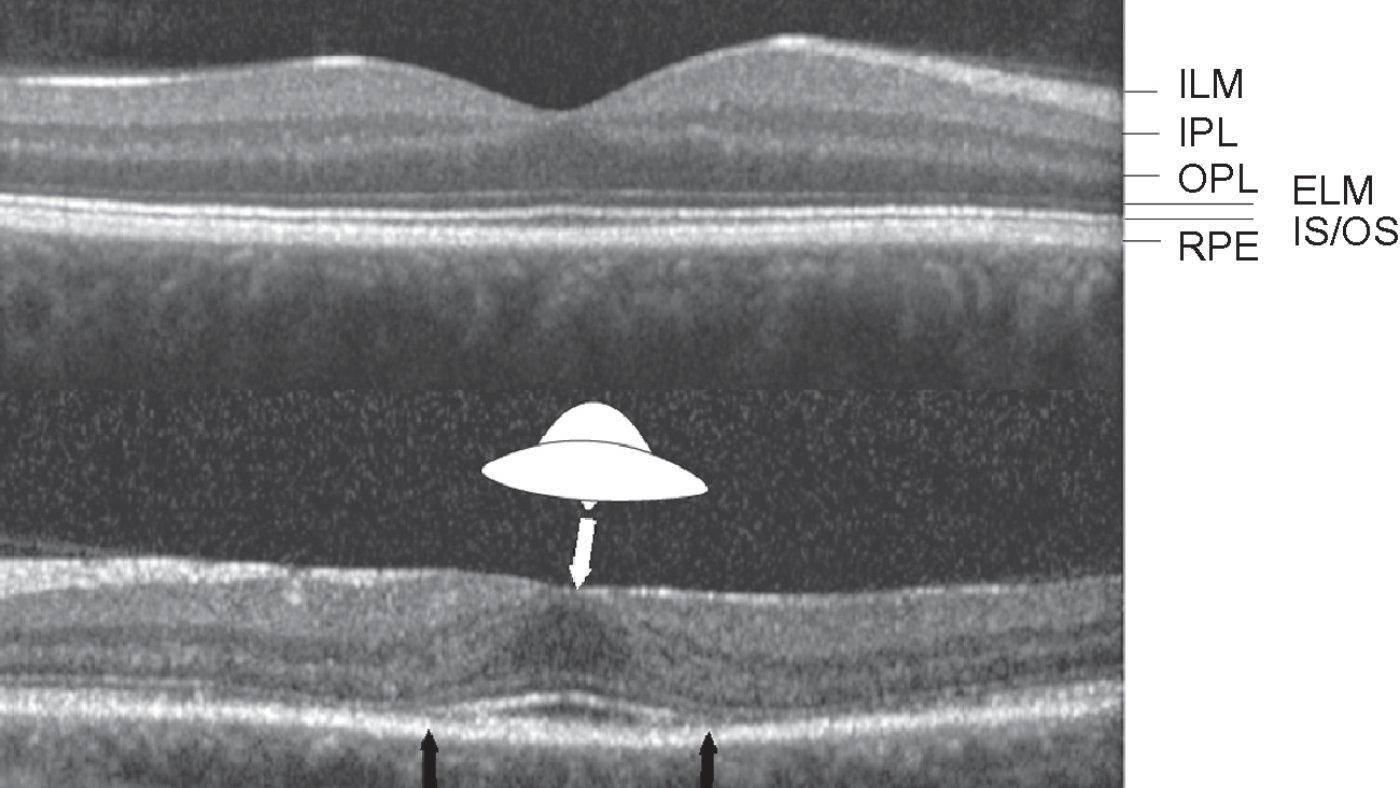

Para a hidroxicloroquina, é bem conhecido, entre os efeitos colaterais, um padrão de alterações retinianas que, apesar de ocorrer numa minoria de usuários, pode comprometer a visão de modo importante e definitivo. A foto que ilustra este post, mostra o chamado “Sinal do Disco Voador” sugestivo de retinopatia cloroquínica à tomografia coerência óptica.